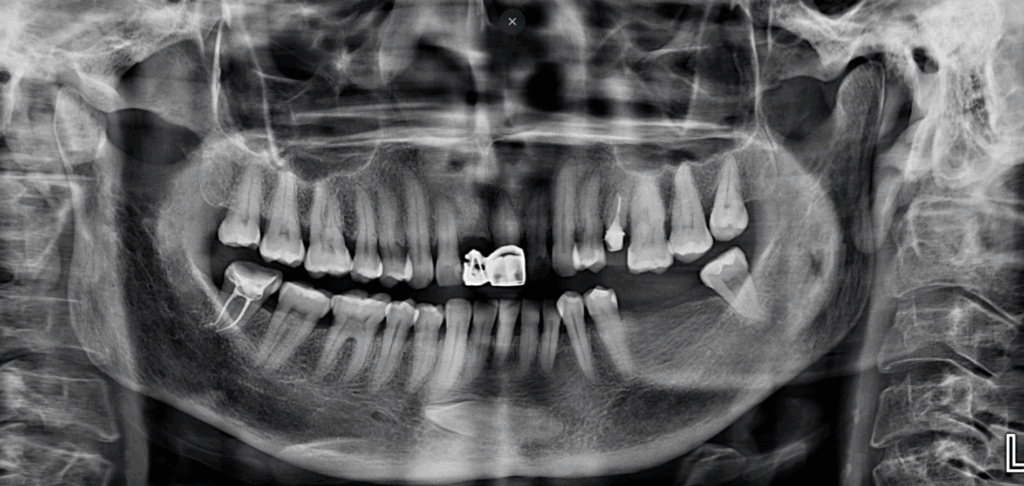

Radiografia Panorámica

A la evaluación de la radiografía panorámica se observa aplanamiento condilar bilateral, neumatización de ambos senos maxilares, presencia de placa mineralizada y reabsorción ósea del proceso alveolar, asimismo se observa múltiples restauraciones coronarias, las piezas 24 y 47 con tratamieto de conductos, pieza 21 con corona protésica, etc. Además, se observa la pieza 33 incluida en posición horizontal y proyectada a nivel de la sínfisis mandibular y con la porción coronaria orientada hacia el cuarto cuadrante a nivel apical de la pieza 43.